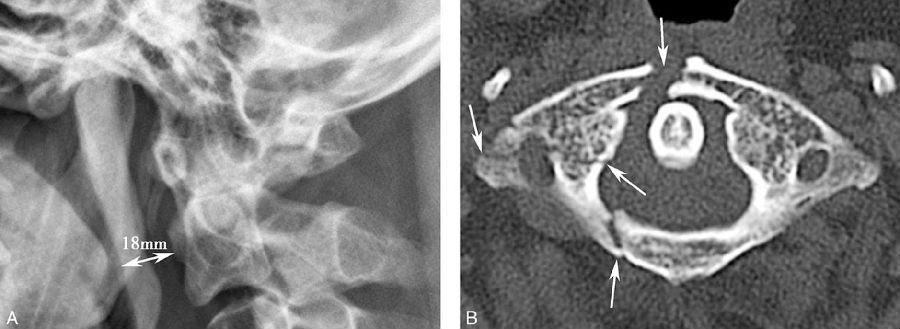

图9 寰椎多发骨折

A. 颈椎X线侧位未显示明显骨折,但椎前软组织厚度达18mm(>7mm),为局部骨折的间接征象;B. CT横断面显示寰椎前弓、后弓、侧块及横突多发骨折(箭)。